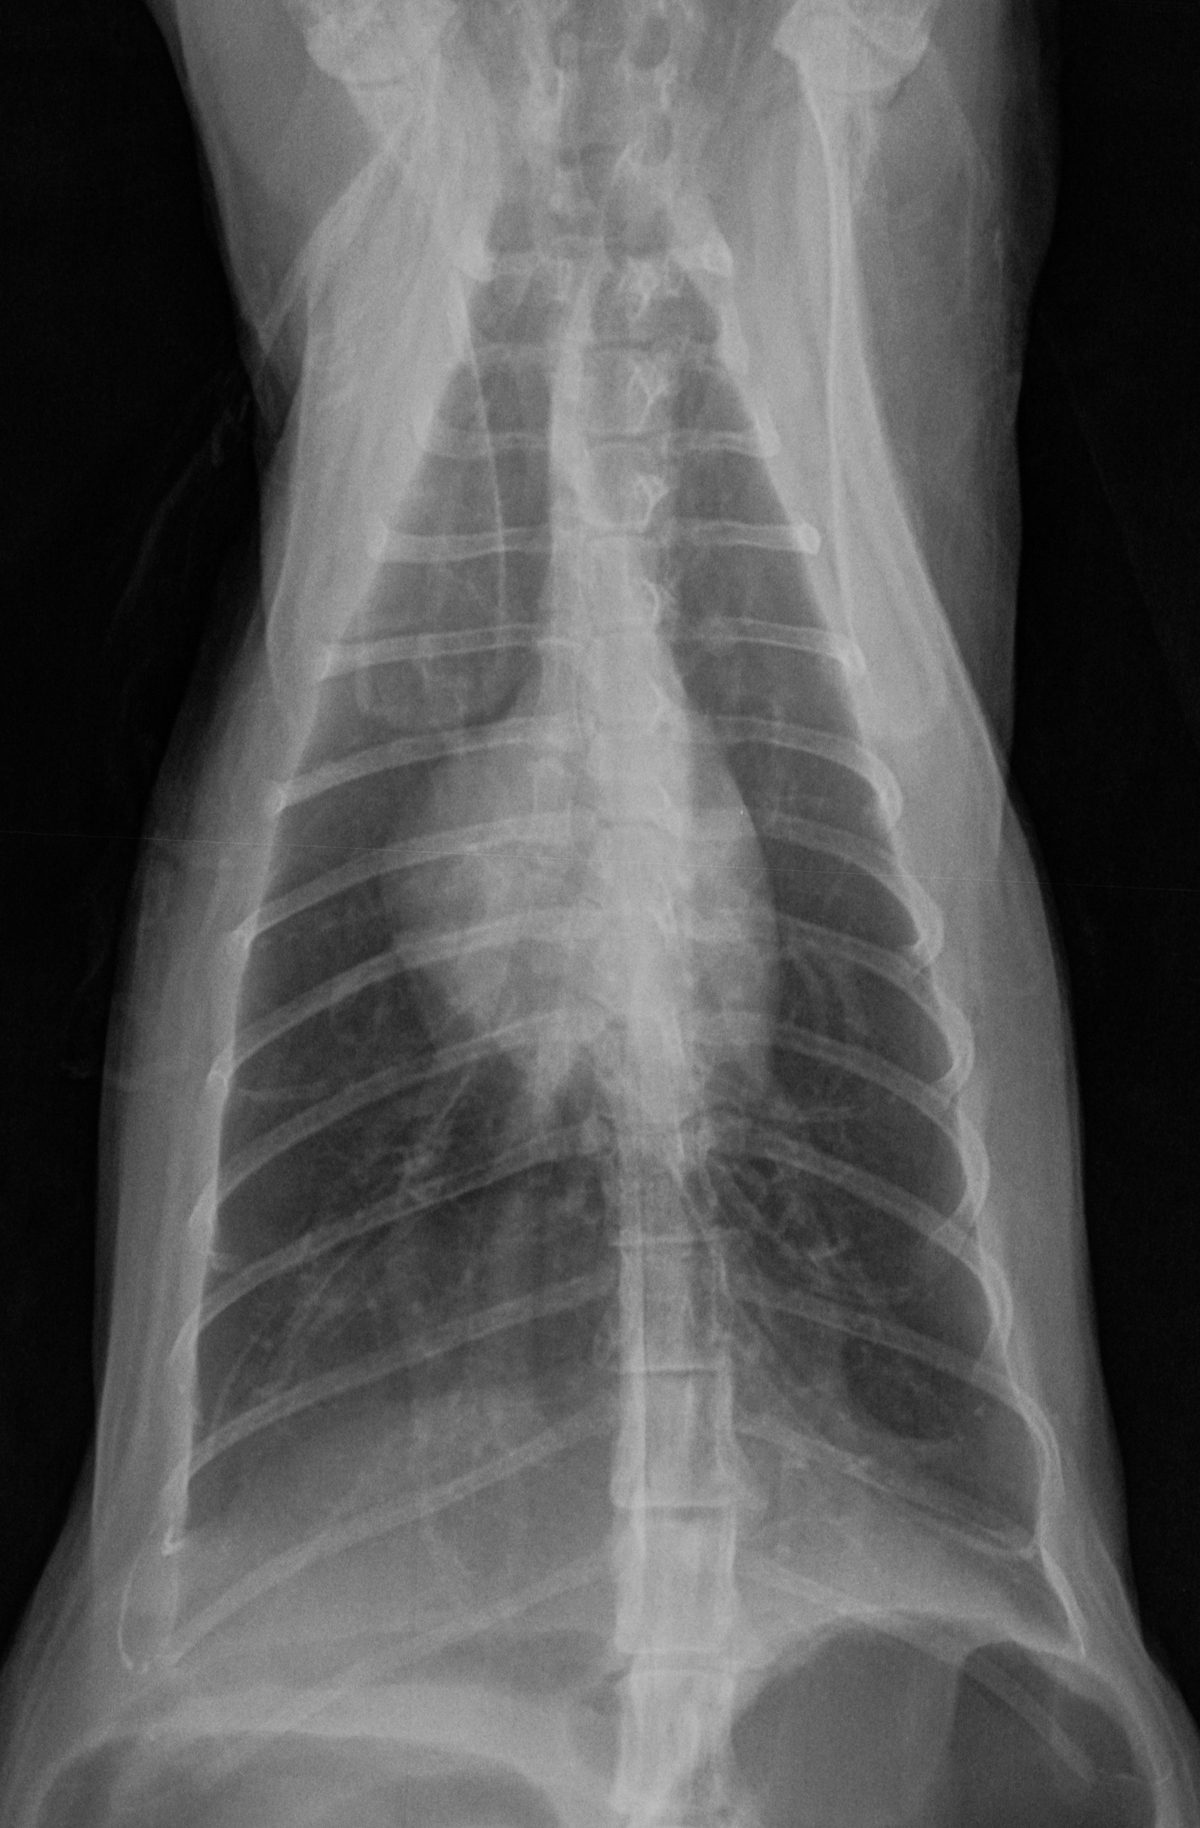

Voici un autre exemple d’hyperinsufflation pulmonaire engendrée par les bronchospasmes et bouchons muqueux qui limitent l’expiration pulmonaire. Cette hyperinsufflation se remarque par la forme de « cloche » du thorax sur la VD. Normalement, le thorax devrait être triangulaire chez le chat. Le diaphragme est aussi aplati sur la latérale. On remarque aussi un patron bronchique léger à modéré, plus facile à voir sur les images magnifiées. Cliquez sur les images pour les voir en haute résolution.